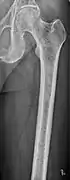

The diagnostic examination of a person with suspected multiple myeloma typically includes a skeletal survey. This is a series of X-rays of the skull, axial skeleton, and proximal long bones. Myeloma activity sometimes appears as "lytic lesions" (with local disappearance of normal bone due to resorption) or as "punched-out lesions" on the skull X-ray ("raindrop skull"). Lesions may also be sclerotic, which is seen as radiodense.[70] Overall, the radiodensity of myeloma is between −30 and 120 Hounsfield units (HU).[71] Magnetic resonance imaging is more sensitive than simple X-rays in the detection of lytic lesions, and may supersede a skeletal survey, especially when vertebral disease is suspected. Occasionally, a CT scan is performed to measure the size of soft-tissue plasmacytomas. Nuclear Medicine Bone scans are typically not of any additional value in the workup of people with myeloma (no new bone formation; lytic lesions not well visualized on nuclear bone scan).

Femur with multiple myeloma lesions

Same femur before myeloma lesions for comparison